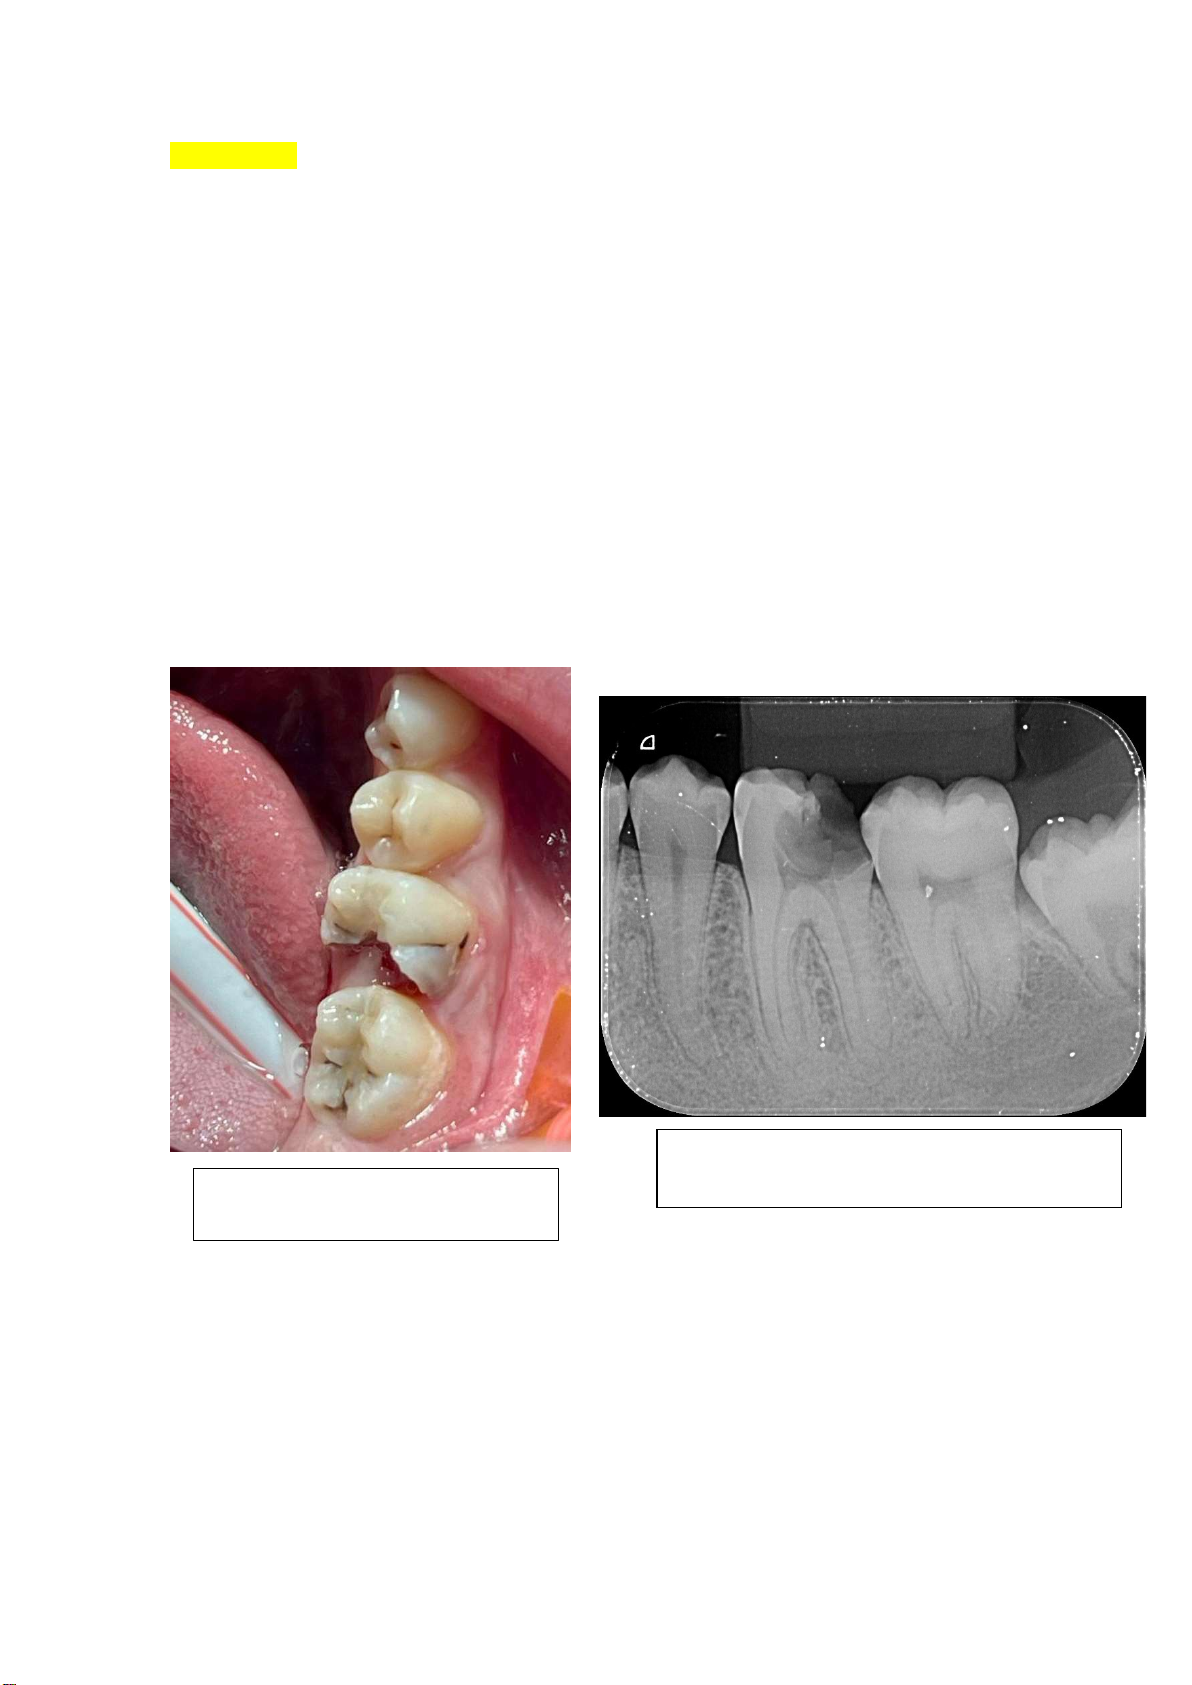

apenas provocadas. Posteriormente realizou-se exames sicos extra e intraorais e clinicamente

observou-se que o dente se apresentava com a coroa parcialmente destruída envolvendo as

faces: oclusal, distal e lingual (figura 1). Logo após, realizou-se as radiografias interproximais e

periapical da região (figura 2).

Figura 1: radiografia periapical- elemento 36

sem a presença de rarefação periapical. Figura 1: Fotografia intrabucal do

elemento.